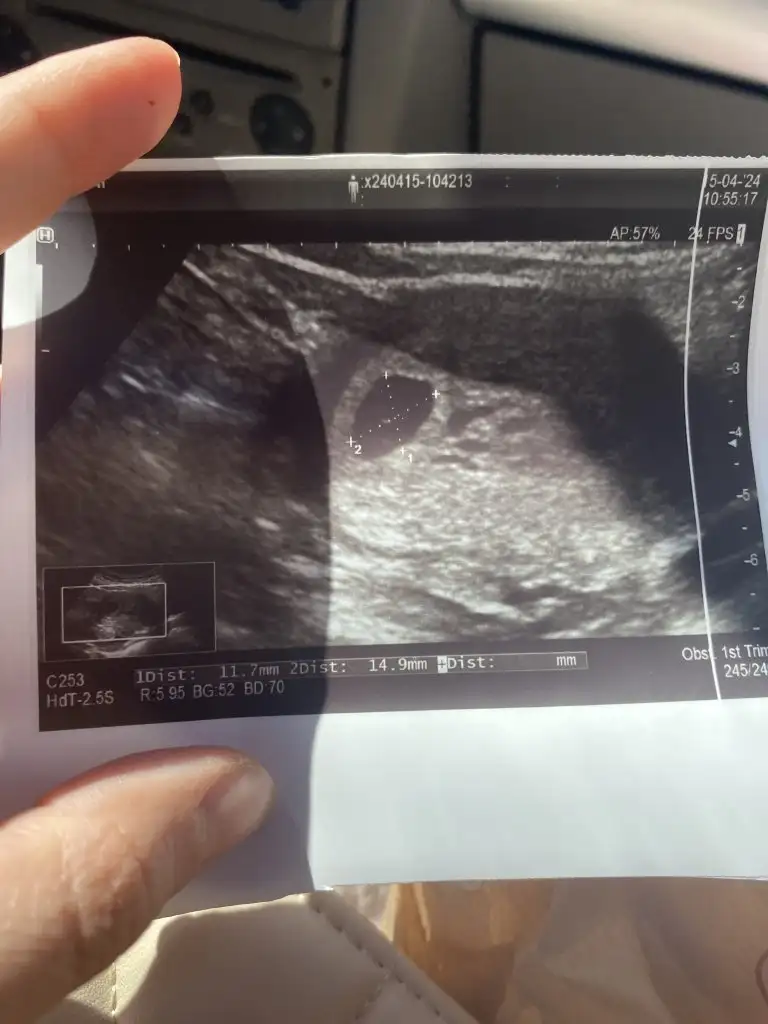

Ya benim kesem biraz uamuk gibi geldi endişe ettim. Bende 30 nisanda kalp atışına gideceğim. Gittiğimde 7+2 olacağız

Dün kese göründü. Telefonda uygumasina göre 5+4'teyiz.

Tahmini doğum tarihi 14 Aralık .

Beni de tabloya eklerseniz sevinirim 🤭